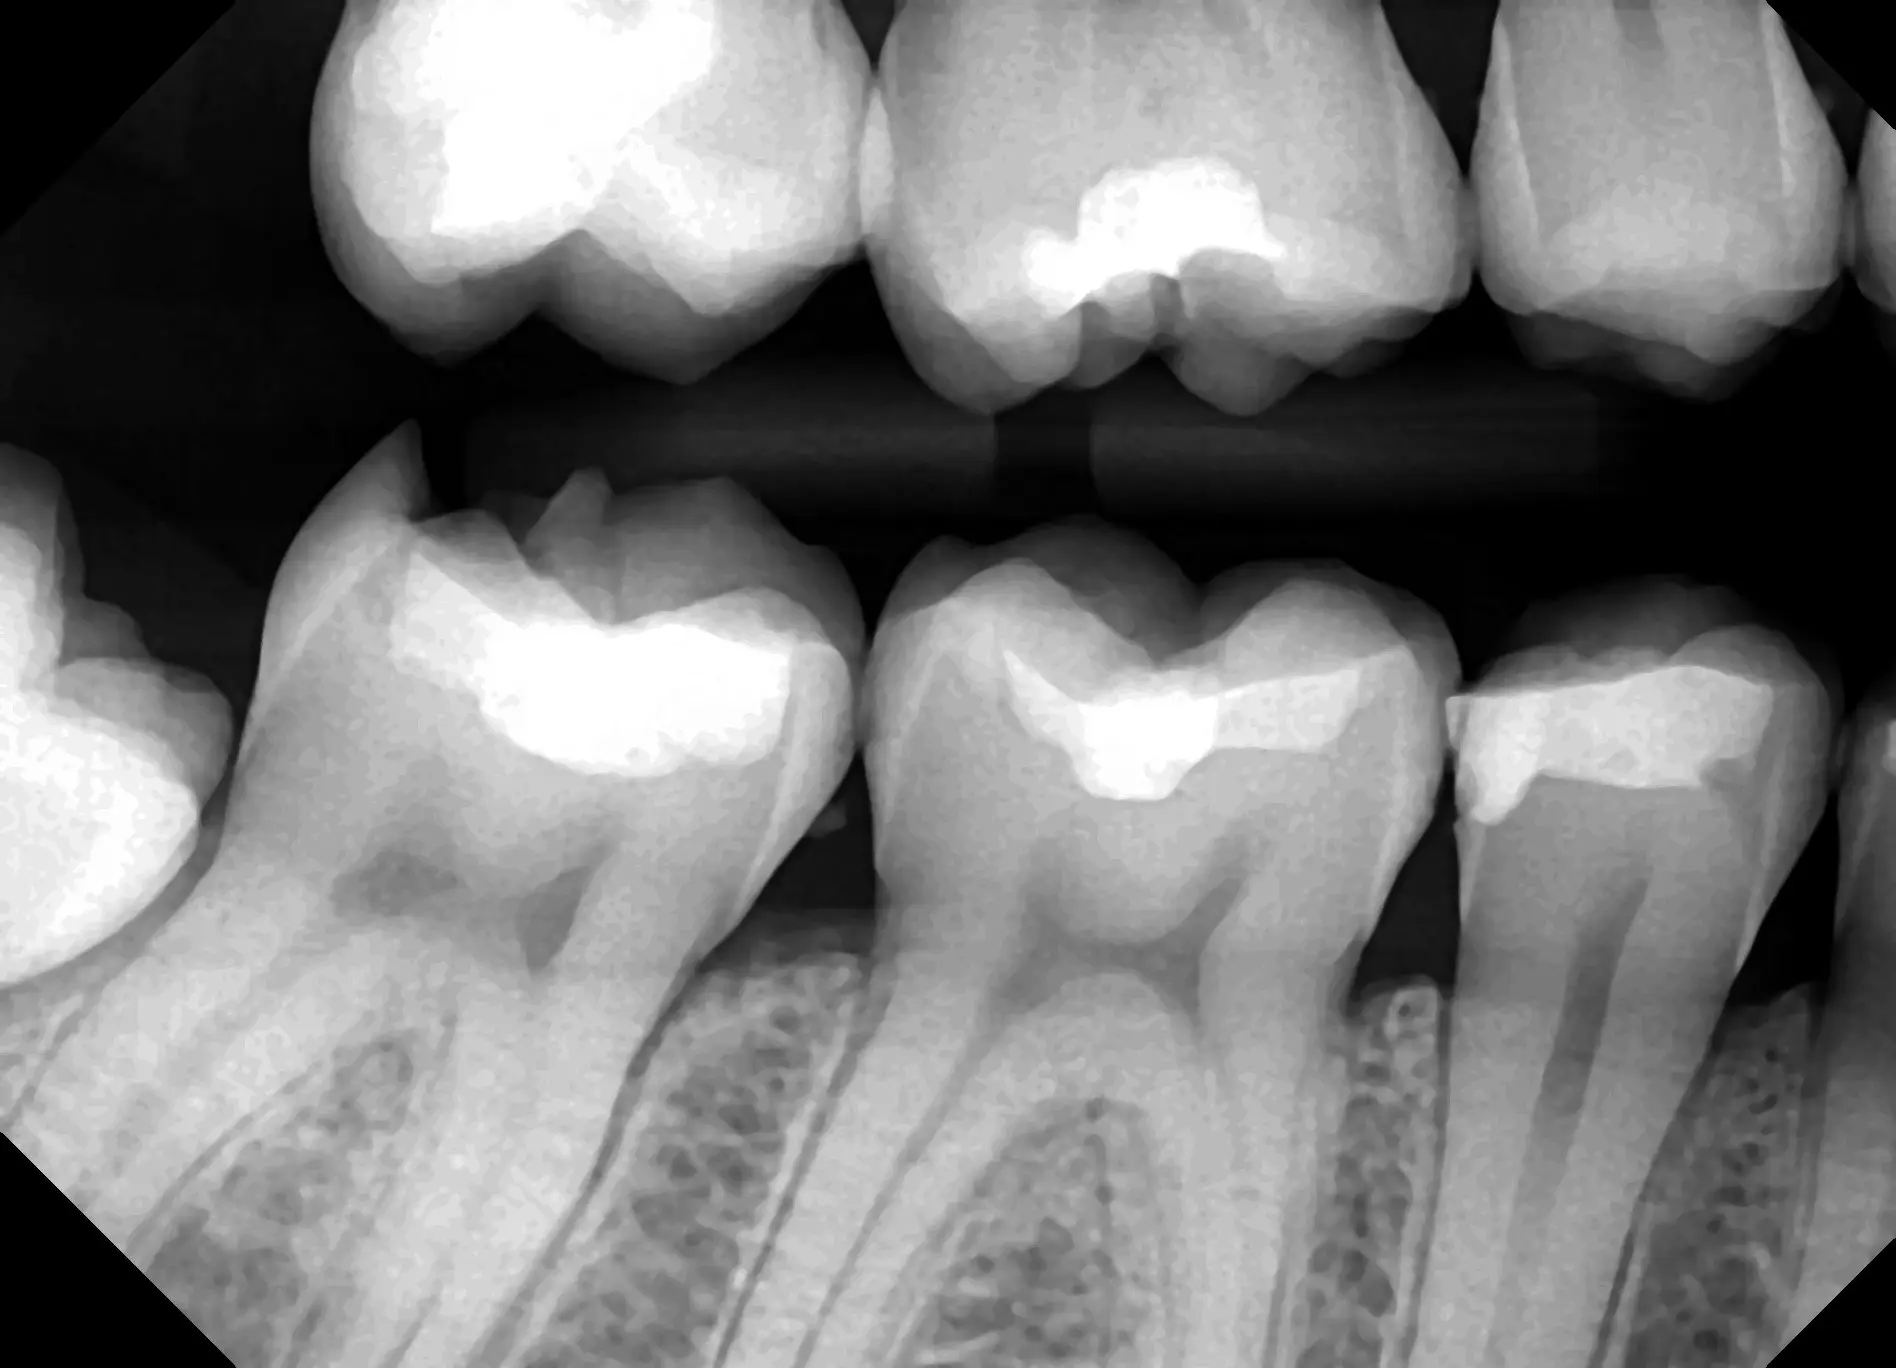

See for yourself the X-ray Gallery from the Dream Sensor!

Click any image in the x-ray gallery below to see the full version.

All images are taken with the DentiMax Dream Sensor and are compatible with the DentiMax Imaging Software and most other imaging software on the market.